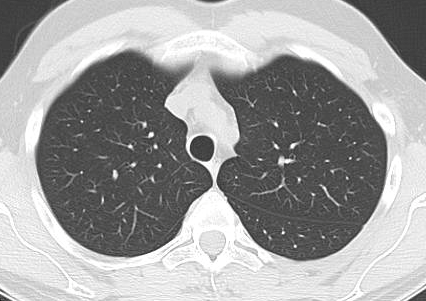

SARS-CoV-2 CT Scan dataset [50]: The dataset was collected from hospitals of Sao Paulo, Brazil, with a total of 2482 CT scans acquired from 120 patients of both genders. It is composed of 1252 scans for patients infected with SARS-CoV-2 and 1230 scans for patients infected with other lung diseases. The CT scans have varying spatial sizes between and , and are available in PNG format. CT scans from this dataset are shown in Figure 7.

COVID19-CT dataset [51]: The dataset consists of a total of 746 CT images. There are 349 CT images of patients with COVID-19 and 397 CT images showing Non-COVID-19, but other pulmonary diseases. The positive CT images were collected from preprints about COVID-19 on medRxiv and bioRxiv, and they feature various manifestations of COVID-19. Since the CT images were taken from different sources, they have varying sizes between and . Figure 8 shows example CT images from the COVID19-CT dataset.